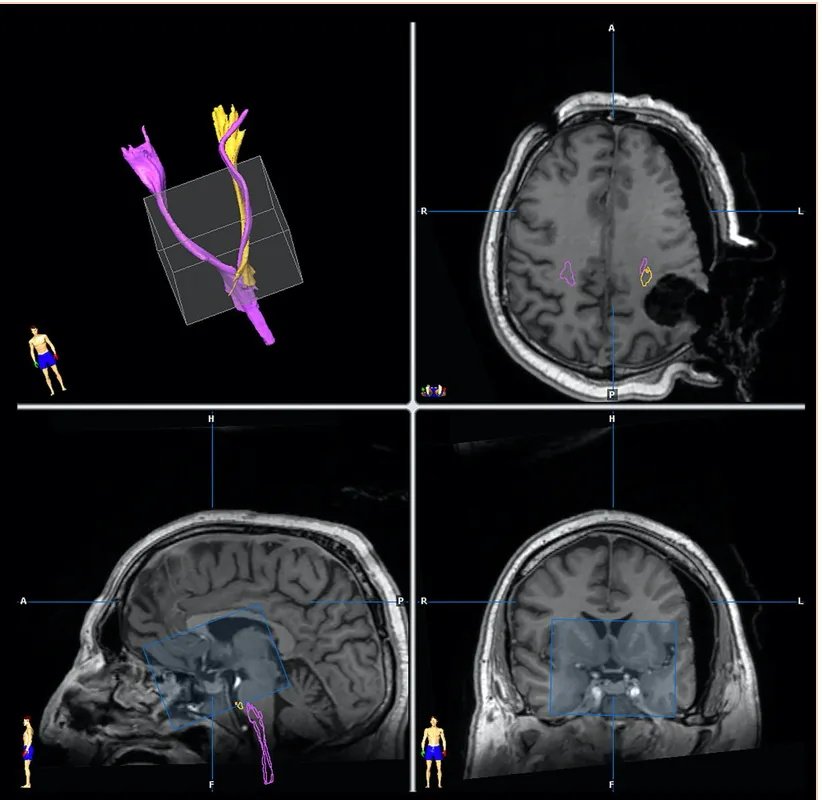

【示意图:术中iMRI成像。进行了术前皮质嵴髓束(CST)(粉红色)和术中(黄色)图像的纤维追踪:由于肿瘤切除后的移位,注意CST的不同位置非常重要】